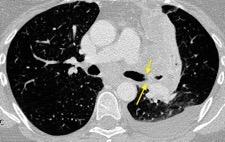

Anatomía

BPI: 75% de normales

La imagen es probable que represente al BPI, a la altura del nacimiento del BLSI.

AV,. The left lateral radiograph of the chest. Part One. Med. Radiogr. Photogr.1979.

La presencia de tumor o ganglios rodeando el BPI hace que este aparezca como mucho más nítido y definido.

Carcinoma microcítico..

Parálisis frénica. Atelectasia parcial de LSI.

Whitten CR. A Diagnostic Approach to Mediastinal Abnormalities. Radiographics 2007 / Marano R et al. Cardiac Silhouette findings And mediastinal lines and stripes. Chest. 2011